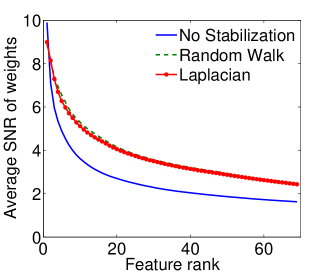

|

|

| (a) Cumulative, | (b) Stagewise (Shared), |

|

|

| (c) Stagewise (Separate), | (d) Stagewise (Separate), |

We now examine the models stability against data sampling and evaluate the stabilizing property of the proposed method (Sec. 6.2). For each fold, we generated samples, each of which was drawn randomly from % of training data. Each example resulted in a model, and the feature weights were recorded and finally the results of all folds – models – were combined. Figs. 5(a–d) show the indices (Eq. (5)) as functions of the rank list size , for all ordinal classifiers. The instability is clearly an issue – the average selected probability drops as more features are included. Using both the Laplacian and random walk regularization methods (Eqs. (9,10)), the improvement in stability is evidenced in all settings. The instability and stabilizing effect were similarly obtained with the indices (Figs. 6(a–d)).